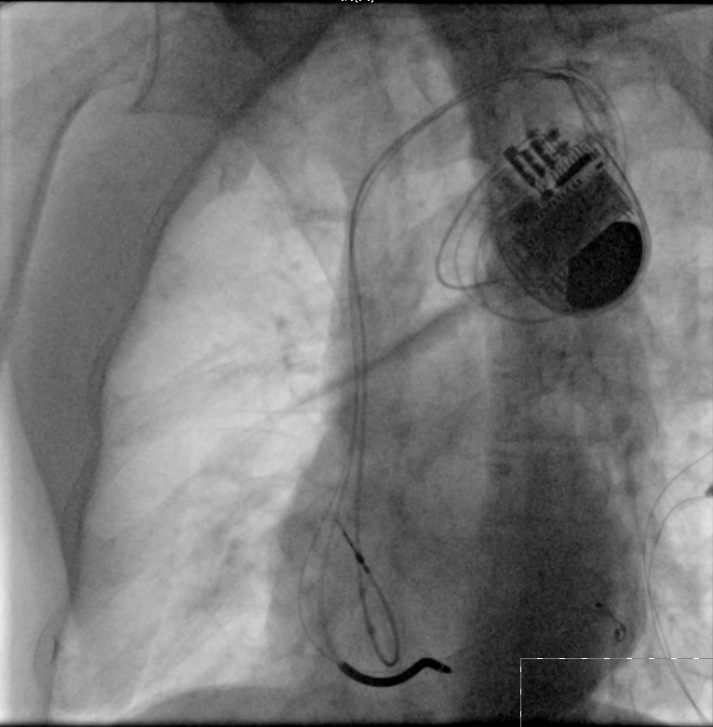

90歲的劉大爺,因為心衰反復(fù)出現(xiàn)呼吸困難及雙下肢水腫,心臟彩超提示左心室舒張末期內(nèi)徑達62mm(正常男性小于55mm),左室射血分數(shù)僅27%,心電圖提示竇性心律,完全性左束支傳導阻滯,單純藥物治療后無效。在瀘州市中醫(yī)院心衰中心接受帶除顫功能的三腔起搏器植入術(shù)及規(guī)范的藥物治療并定期隨訪,現(xiàn)心臟彩超提示左心室舒張末期內(nèi)徑恢復(fù)到57mm,左室射血分數(shù)恢復(fù)到45%。目前,劉大爺散步、養(yǎng)花、做家務(wù)已經(jīng)沒有了呼吸困難,也沒有再出現(xiàn)雙下肢水腫及腹脹,也不用再頻繁住院,提高了生活質(zhì)量。

帶除顫功能的三腔起搏器植入術(shù)(CRTD)